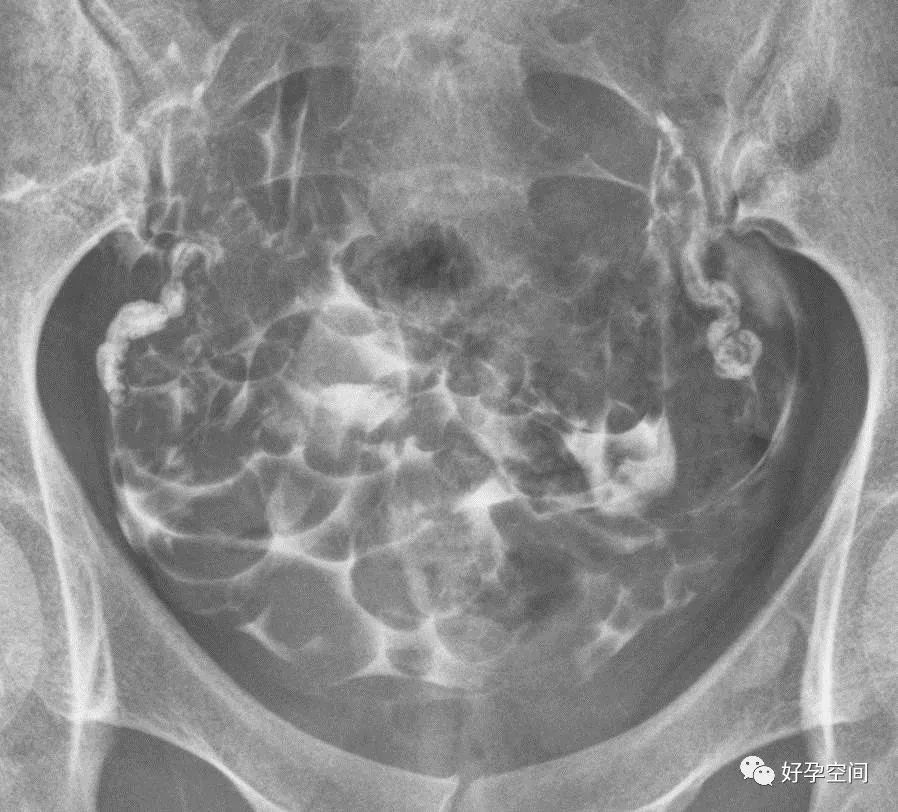

二、子宫输卵管造影正常

盆腔平片

子宫相

输卵管相

弥散相,延迟5分钟摄片,双侧输卵管内可见较多造影剂

弥散相,延迟10分钟摄片,双侧输卵管内可见少量造影剂

弥散相,延迟20分钟摄片,双侧输卵管内基本没有造影剂残留